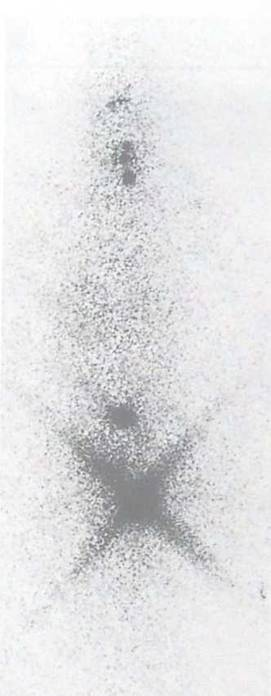

病例五:单发性骨转移瘤:鼻咽癌

右下肢疼痛一周,x线片显示阴性,骨扫描显示右股骨上端骨转移。